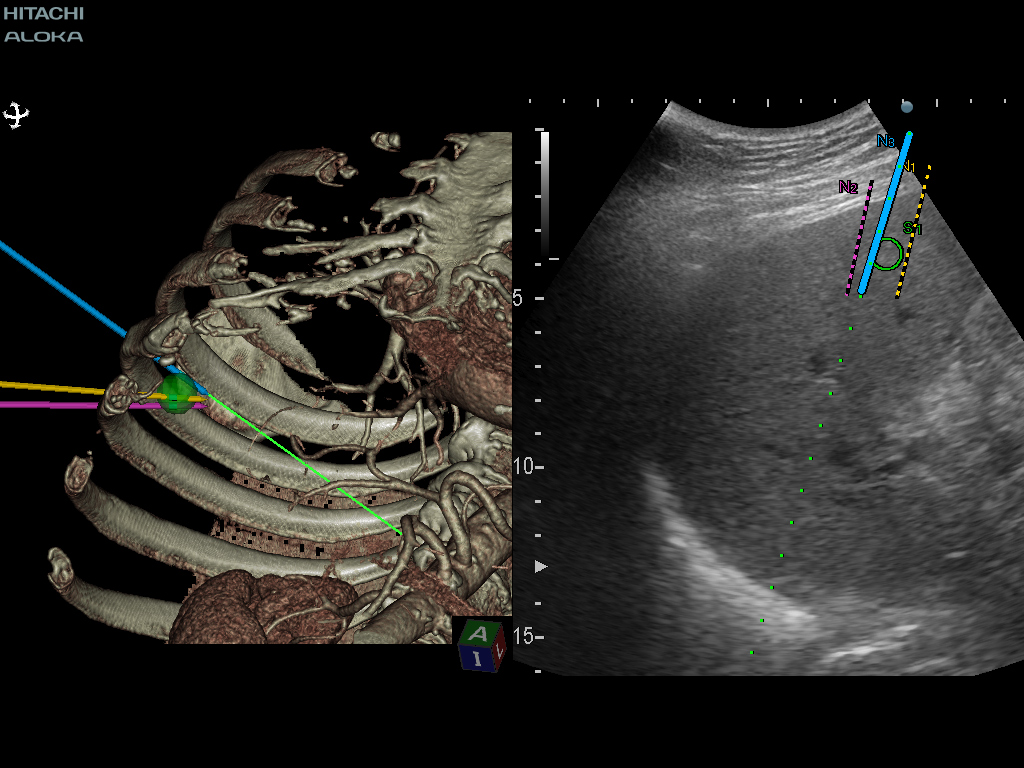

태아의 뇌 검사에서 실시간 가상 초음파 검사 (RVS)는 중뇌의 형성 (예 : pons and tegmentum), 특히 측두엽의 회전과 같은 특정 해부학 적 특징을 인식하는 데 도움이 될 수 있습니다.